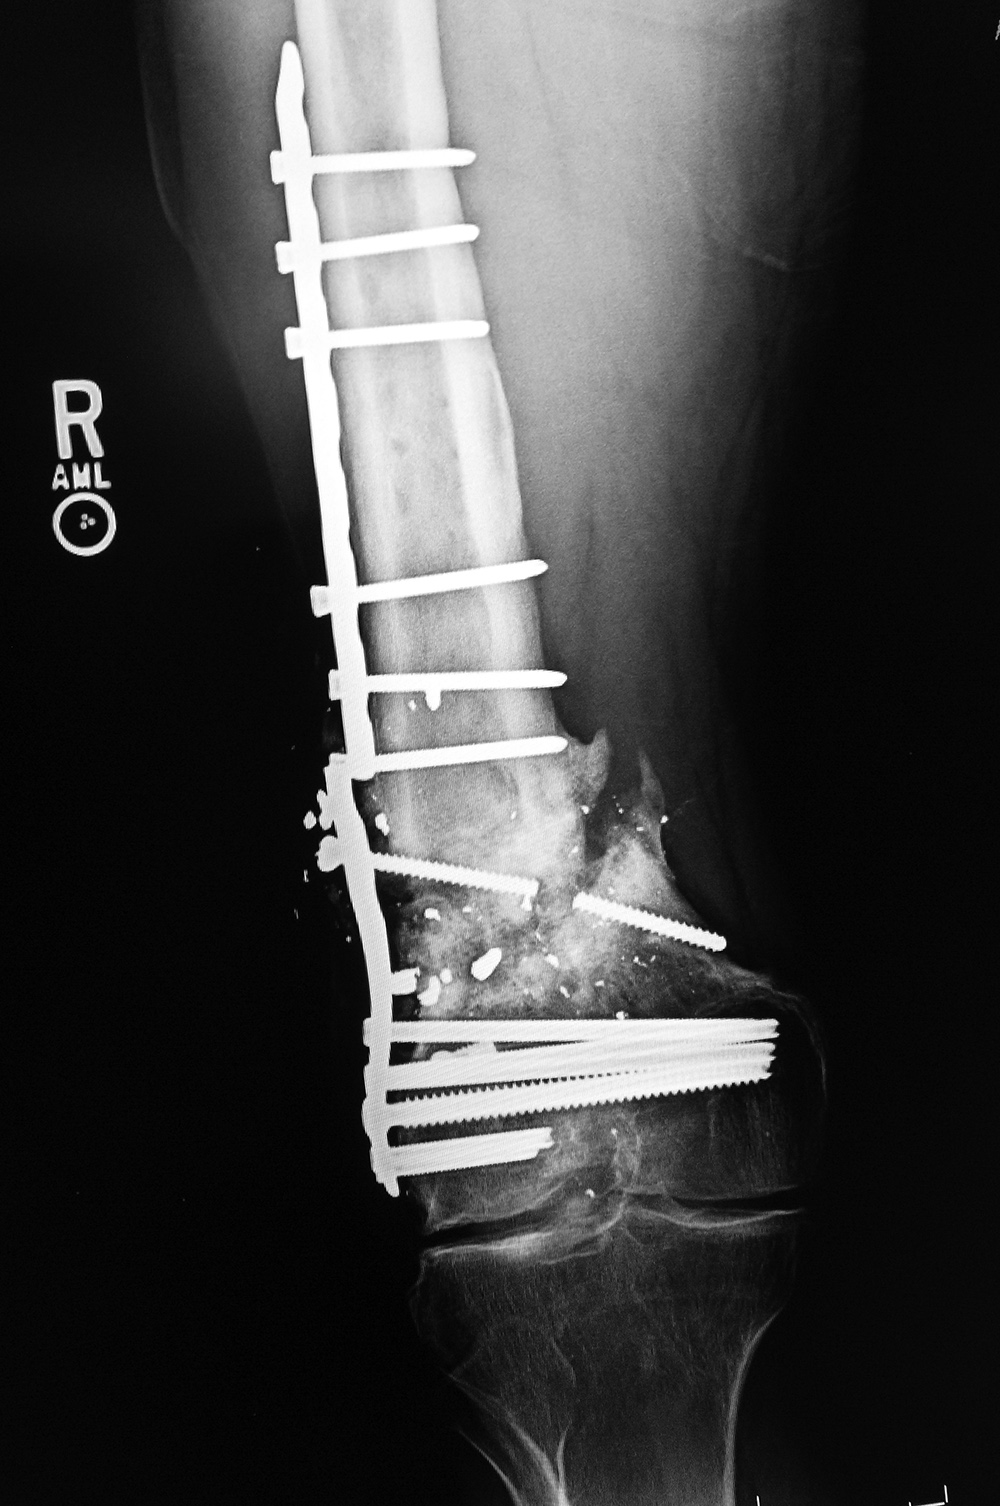

| Right femur periarticular plate breakage and chronic fracture nonunion |

| 36 year-old man with bullet wound in 2003 complicated by femur fracture infected non-union treated by multiple attempts with external fixation and open reduction and internal fixation (ORIF). Radiography 12 years later shows chronic fracture hypertrophic nonunion, multiple shrapnel fragments, and breakage of a periarticular fixation plate. |